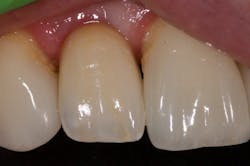

I began centering my consultation appointments on options that subsequently allowed patients to actually sell themselves on the implant treatment modality. I would present the tooth-replacement options of endo/core/crown, extraction/bridge, and extraction/implant ... and then I would explain the pros and cons of each. What I found is that patients overwhelmingly chose the root-replacement option—dental implants—over the old-school (drill-o-dontics) to reconstruct their missing tooth. Patients actually wanted an implant once they were armed with all the complete information they needed to make their decision. Having models on hand that show the difference between each option is highly effective, especially for those patients who are visual learners.

When your treatment plan includes only the next most conservative procedure—instead of all treatment options—inevitably you will do lots of work “saving” badly damaged roots and roots with guarded or poor long-term prognosis. Some patients may applaud or highly value these efforts on your part, but I have met many more who are glad to skip the possibility of re-treatment, root fracture, core failure, etc. You'll find that many patients will choose implants as an expedient and efficacious alternative to restoring the root with diminished or guarded prognosis, rather than spend their money over and over again on an undesirable tooth.

This is the paradigm shift in thinking that initiated big changes in my practice. In 2010, my little office restored 38 implant fixtures. By 2017, we were restoring closer to 200. What a difference! When patients began to realize they had treatment possibilities that may have a better long-term prognosis than the traditional replacement options, implants became a definite green light for them.